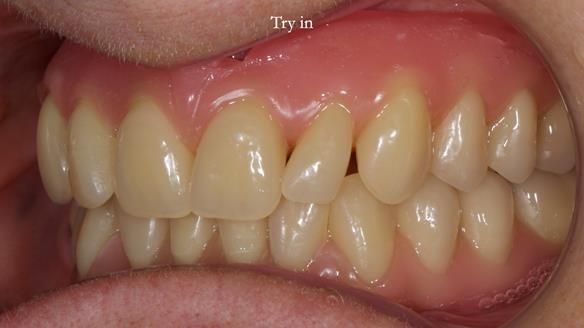

However, once Rowan and I reviewed the remaining metal crown on tooth 46, we realised it would make an ideal abutment for a gasket denture. By reshaping the lingual surface of the crown, we created an excellent gasket seal.

This approach worked far better than the proposed ring-clasp design - improving retention, comfort, and aesthetics while keeping the design clean and simple.

- The gasket seal around 46 was made using retention.sil 200, producing a precise, cushioned fit.